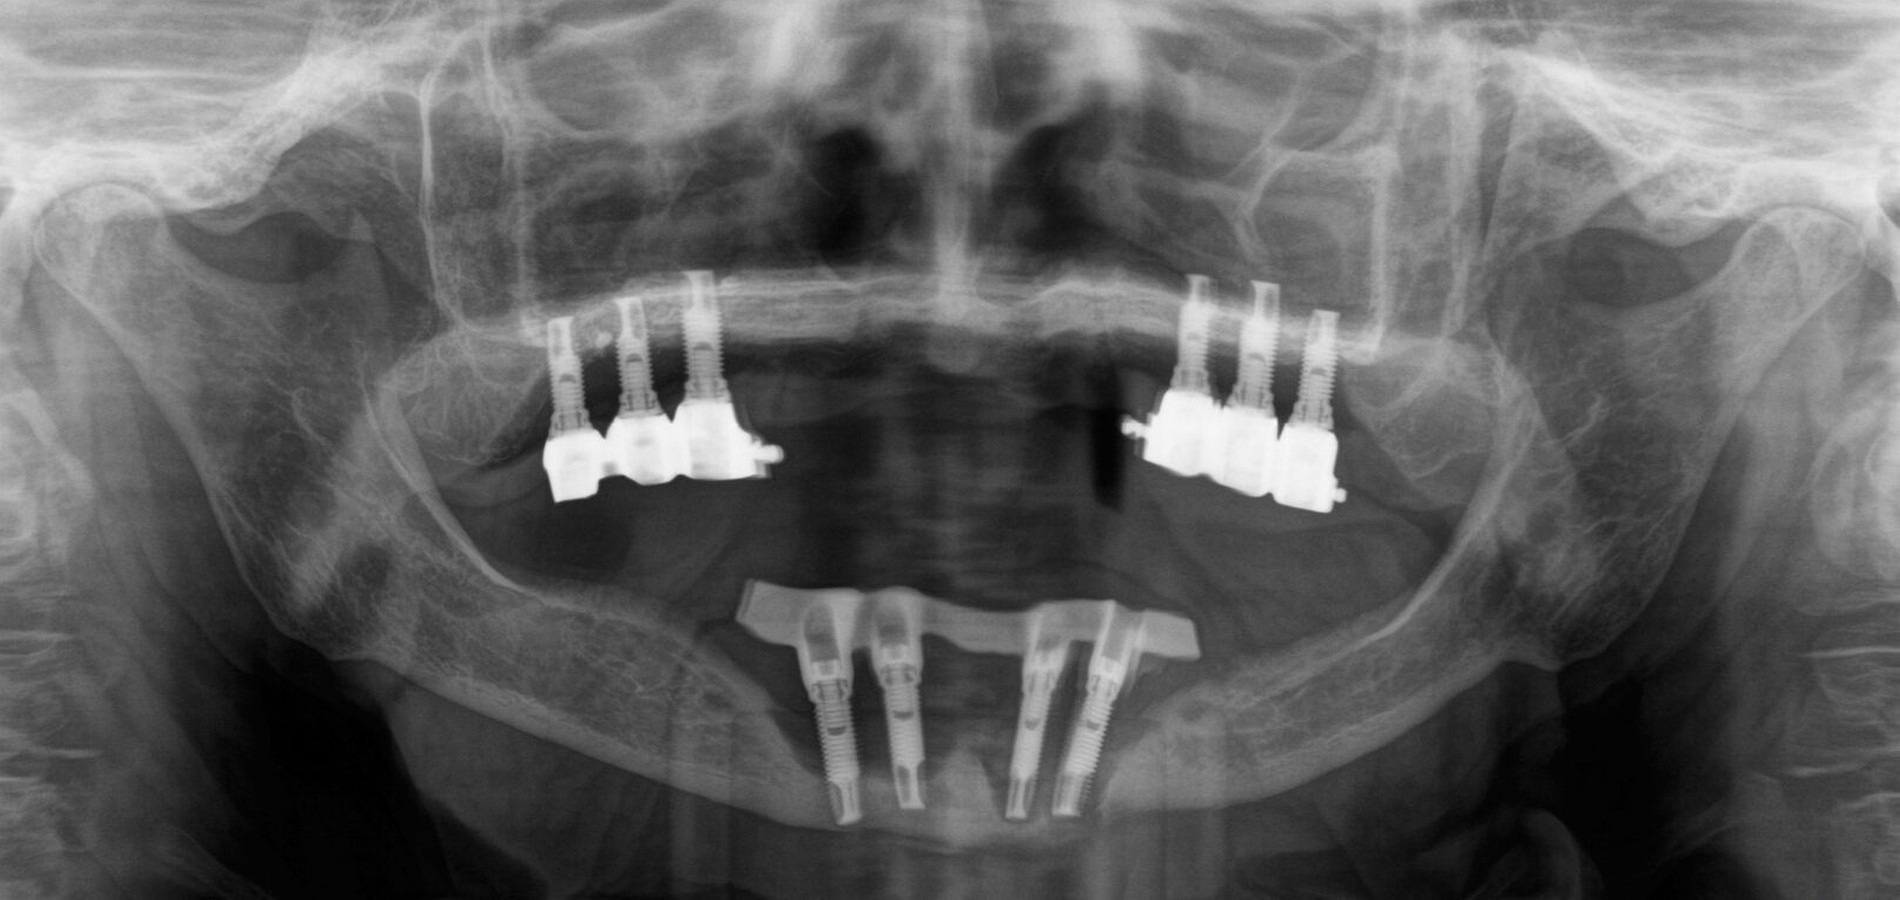

In der Panoramaschichtaufnahme zeigten sich an allen Implantaten ausgeprägte Knocheneinbrüche. Die Implantate in regio 33 und 32 waren vollständig von Osteolysesäumen umgeben, distal des Implantats in regio 33 stellte sich eine knöcherne Unterbrechung des Unterkiefers dar. Die anschließend angefertigte CT-Bildgebung des Unterkiefers und der Nasennebenhöhlen zeigte ausgeprägte osteolytische Säume um alle Implantate im Ober- und Unterkiefer mit einer knöchernen Unterbrechung des corpus mandibulae in regio 33. Weiterhin kamen weichgewebedichte Verschattungen beider Kieferhöhlen (links vollständig, rechts basal) und des sinus frontalis et ethmoidalis links, die mit einer chronischen Sinusitis vereinbar waren, zur Darstellung.